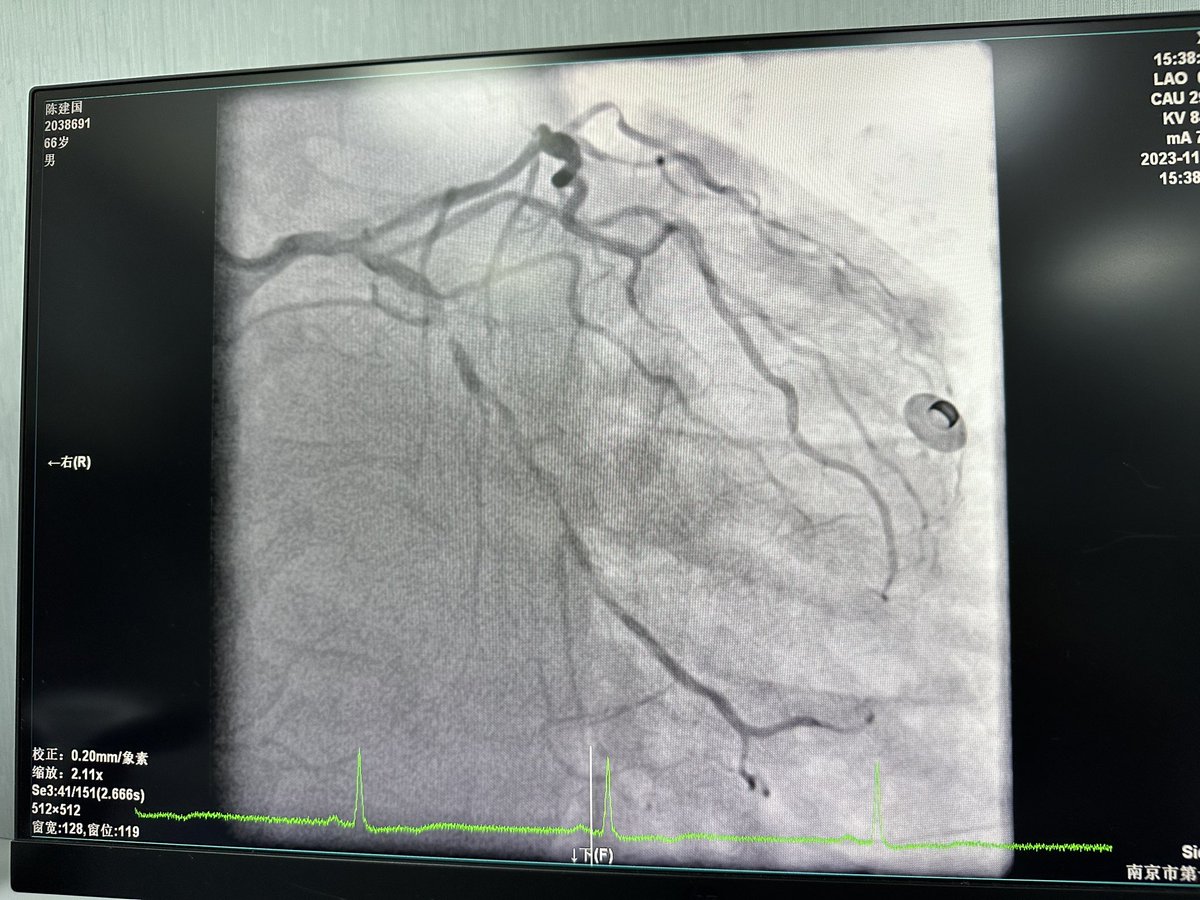

1. My second Live case at #CBS staged lms following successful cto rca. Syntax score 44, heavy calcium, #radialfirst 7fr, ivus guided. Had initially planned to rotate lms/ lad. Ivus- 180 degree ca at worse in focal area do decided balloon + lithotripsy . @aymanka @billgogas